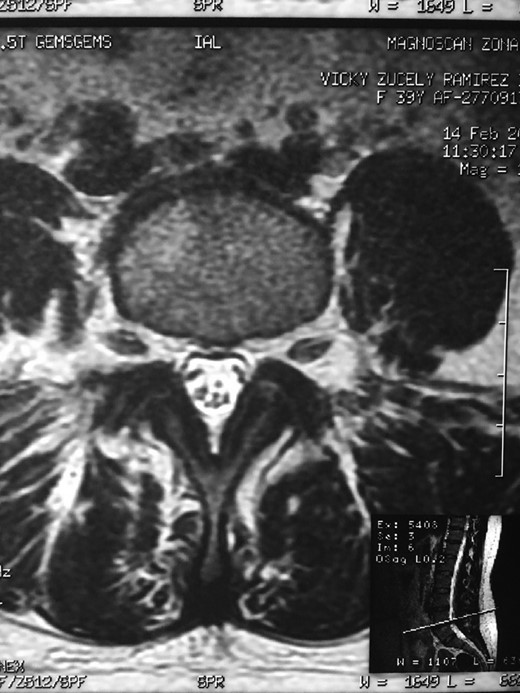

A 42-year-old female presented to the clinic with a history of chronic low back pain. She reported no relevant medical history. She had already been treated in the last 4 years by general practitioners with analgesics and home based physiotherapy with no satisfactory results. She had two previous admissions to the emergency department where morphine was prescribed to control the pain on her lower back. She was under ambulatory treatment with diclofenac, and tizanidine with partial relief of symptoms. Her main complaint was pain on the lower lumbar back with no radiation to the lower extremities. In her physical evaluation she presented limitation to full rotation and bending of the lumbar spine due to pain. Lasegue sign was negative, sensitivity, reflexes, sagittal balance, distal muscular strength and pulses were normal. Radiographs showed an overdeveloped left transverse process of the fifth lumbar vertebra which contacts with the sacrum at the left sacral wing with signs of degeneration at the same site (Fig. 1). Magnetic resonance imaging (MRI) studies were obtained (Figs 2–5). The patient was taken to the operating room where infiltration with 1 mL of lidocaine and 40 mg of Triamcinolone was performed in the pseudoarticulation between the left transverse process and the sacrum under fluoroscopic guidance. She reported a complete relief of pain after the procedure. At three months follow-up she was managed with strengthening and stabilizing exercises for the lumbar spine and postural education was initiated. She remains asymptomatic at her 12 months follow up.

Showing the protective effect of the limitation of the motion in the distal disc to the anomaly.

The partial fusion at the lower part of the lumbosacral transition produces important alterations in normal biomechanics at the levels immediately above and below the LSTV. Changes such as hypermobility and abnormal torque moments are present at the level above the LSTV, predisposing it to early degeneration (early disc pathology and facet joint degenerative disease). Restricted movement below the LSTV produces a protective effect against degeneration of disc and facets and is related to changes (facets are smaller and coronally oriented) in the dimensions of the lower level facet joints [7]. These alterations can be verified in the adjacent levels of the LSTV in our patient.